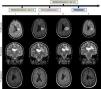

RM cerebral: evolución de la lesión (secuencias FLAIR, T2 y T1 gadolinio) al ingreso (1), tras tratamiento con un pulso de metilprednisolona intravenosa (2), tras tratamiento con inmunoglobulinas intravenosas (3) y tras tratamiento con rituximab (4). Lesión heterogénea con seudohalos agrupados-confluentes (1 y 2) que evolucionan a áreas quístico-malácicas (3 y 4), afectando a corona radiada y centro semioval izquierdos con extensión al cuerpo calloso. Tamaño de 3cm en su diámetro máximo al ingreso (1) que aumenta hasta 4,1cm a pesar del tratamiento (3) y posterior reducción a 3cm tras rituximab (4). No edema perilesional ni efecto masa. Ausencia de realce tras la administración de contraste al ingreso (1) con posterior realce parcheado intra y perilesional a pesar de corticoesteroides e inmunoglobulinas (3) que desaparece tras tratamiento con rituximab (3).

Se presenta el caso de una mujer de 28 años, sin antecedentes de interés, que consultó por instauración subaguda y progresiva de hemiparesia derecha y disartria, como traducción clínica de una lesión seudotumoral. La resonancia magnética (RM) inicial (fig. 1 [1]) mostró una lesión heterogénea afectando a corona radiada y centro semioval izquierdos y al cuerpo calloso, sin edema perilesional, ni efecto masa y sin captación de gadolinio. Se realizaron analítica de sangre, punción lumbar (con estudio de bandas oligoclonales), hemocultivos y cultivos de líquido cefalorraquídeo (LCR), tomografía computarizada (TC) y tomografía por emisión de positrones/tomografía computarizada (PET/TC) de cuerpo completo y ecocardiograma, con resultado normal o negativo. Se incluyó estudio de inmunodeficiencias y de autoinmunidad (sistémica, anticuerpos antineuromielitis óptica, antiglicoproteína de la mielina oligodendrocítica [MOG], onconeuronales y antisuperficie neuronal), PCR de VVZ y VHS en LCR y serologías de VIH, VHC, VHB, CMV, lúes, Toxoplasma gondii, Borrelia burgdorferi, QuantiFERON® y PPD, negativos. Tras descartar razonablemente la causa infecciosa, con datos radiológicos sugestivos de lesión seudotumoral inflamatoria se inició tratamiento inmunosupresor (figs. 1 [2 y 3]): 2 pulsos de 1g de metilprednisolona intravenosa y un ciclo de inmunoglobulinas intravenosas (IgIV). Tras 5 semanas, sin respuesta terapéutica y con progresión clínica y radiológica (fig. 1 [3]) (aumento del tamaño lesional y captación de contraste) se realizó una biopsia cerebral (fig. 2), con hallazgos compatibles con proceso inflamatorio desmielinizante1,4 y ningún dato histológico de malignidad. Posteriormente se inició tratamiento con rituximab, con mejoría clínica progresiva. La RM cerebral (fig. 1 [4]) un mes después objetivó disminución del tamaño lesional y ausencia de captación de contraste. La paciente fue dada de alta hospitalaria con diagnóstico de lesión inflamatoria seudotumoral. Permanece en seguimiento por neurología, sin nuevos eventos hasta la fecha actual.